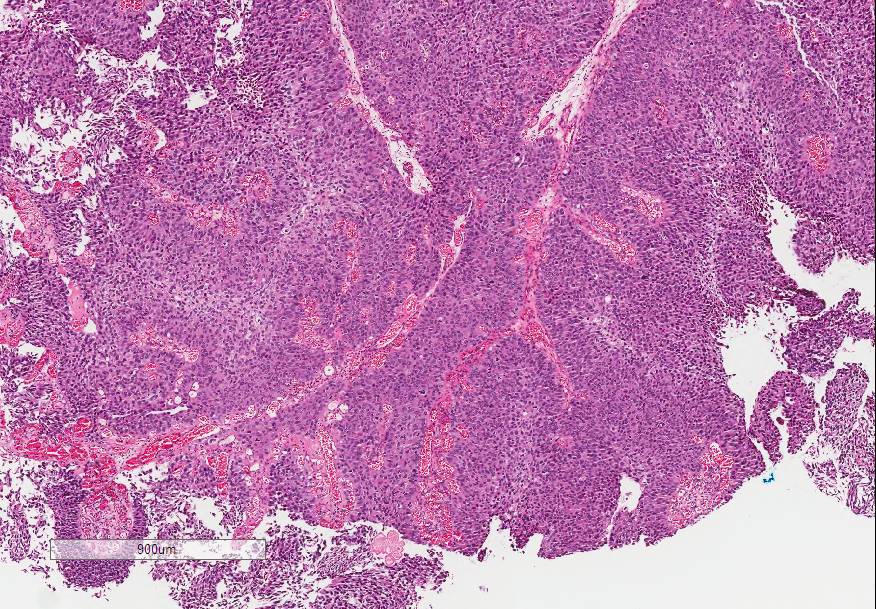

Bladder Papillary Lesions

Case ID: 646